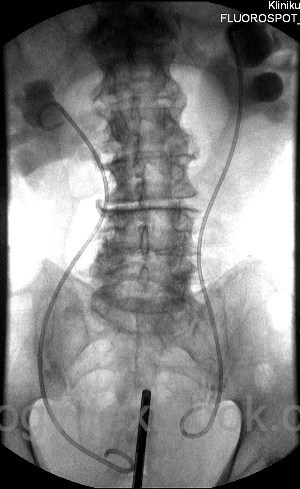

Ureteral stents are thin catheters placed within the ureter to ensure urinary drainage from the renal pelvis. They maintain urinary transport along the ureter and bypass obstructions. Internal ureteral stents drain urine from the renal pelvis into the bladder [Fig. DJ stent], whereas external ureteral stents divert the urine into a collection bag via the urethra or transcutaneously.

An internal ureteral stent is a thin, flexible tube in the ureter with two curled ends located in the renal pelvis and bladder to maintain its position. Due to its characteristic shape, it is also known as a double-J or DJ stent.

Both ends curl (“J-shaped”) to anchor the stent in the renal pelvis and bladder. Side holes allow urine drainage. Some models are open-ended, enabling wire-guided exchanges, while others are closed-ended.

After retrograde pyelography, a guidewire is advanced into the renal pelvis using the working channel of the cystoscope. The stent is then advanced over the wire using a pusher until the proximal curl is placed into the renal pelvis. Withdrawal of the guide wire allows the distal end to coil in the bladder. In difficult cases (e.g., strictures, kinking), hydrophilic or stiff wires may be necessary. If retrograde stenting fails, percutaneous nephrostomy or antegrade insertion of the ureteral stent are the remaining options.